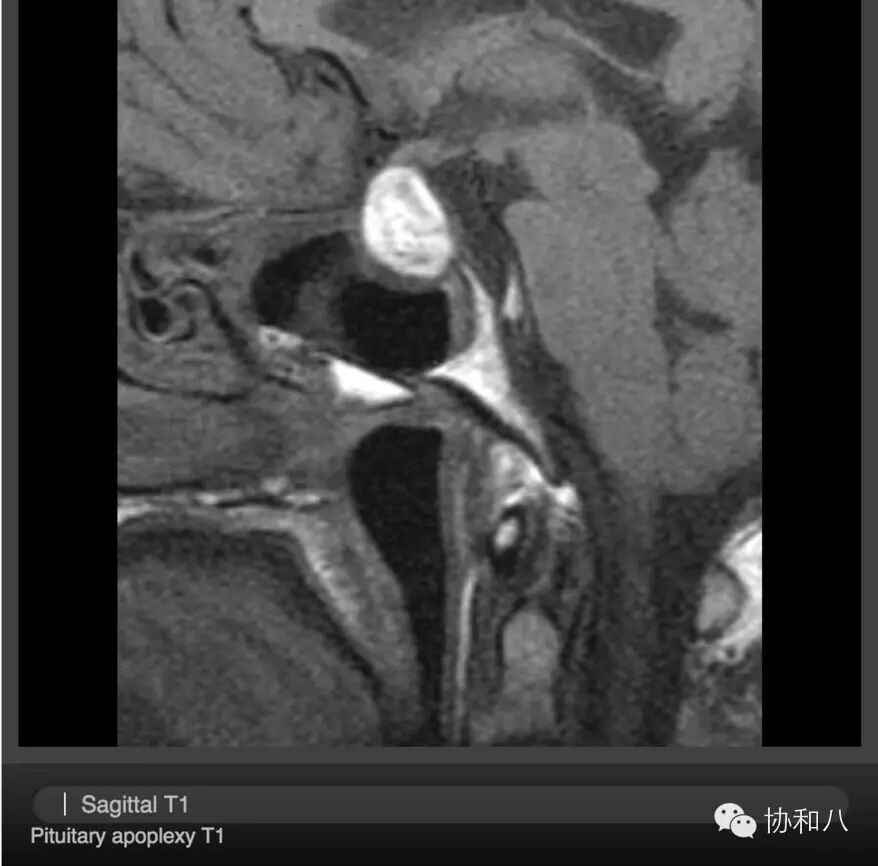

A. 矢状位T1WI

可见垂体增大,在T1W1表现为高信号,符合出血表现